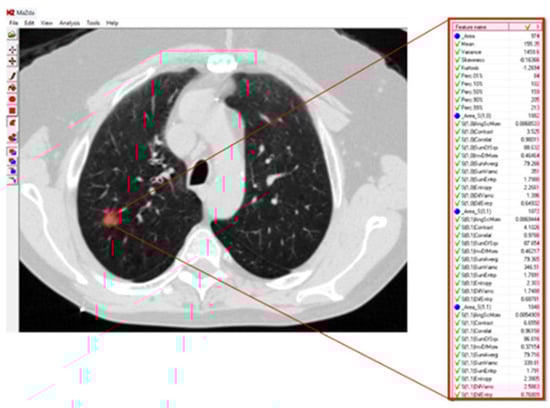

Malignancy in Ground-Glass Opacity Using Multivariate Regression and Deep Learning Models: A Proof-of-Concept Study

Background/Objectives: Ground-glass opacity (GGO) refers to areas of increased lung opacity on computed tomography (CT) scans. Distinguishing malignant from benign lesions using CT scans remains significantly challenging. This study aims to compare the performances of a linear multivariate statistical regression and an AI deep learning method in their abilities to predict GGO malignancy, given a set of pixel features extracted from CT scans. Methods: This retrospective study investigated patients from the Carmel Medical Center with findings of GGO nodules in their lung CT scans. Forty-seven consecutive patients were found to have either pure or part-solid GGO lesions, as defined by two independent radiologists. After manually segmenting the GGOs in the CT scans, pixel features were extracted using the MaZda software package, which analyzes six different image texture features. These textural variables were then compiled as input for the multivariate statistical regression. Additionally, an AI deep learning method, developed by our group and hosted on the cloud, was applied to the CT images containing the GGOs. Results: Among the 47 patients, 32 were diagnosed by pathology with malignant lesions and 15 with benign findings. Using the multivariate statistical regression, we identified 19 variables with statistically significant or near-significant differences through univariate analysis. In subsequent multivariate analyses, two independent variables that could distinguish between benign and malignant GGO lesions were identified: S(4,4)AngScMom (p = 0.012) and WavEnLH_s-2 (p = 0.008). The regression formula based on these two variables yielded a sensitivity of 91% and a specificity of 67% AUC: 0.8 (95% CI: [0.65, 0.94]). The AI deep learning model demonstrated a sensitivity of 100% and a specificity of 80% AUC: 0.96 (95% CI: [0.86, 1.00]). Conclusions: This proof-of-concept study demonstrates the superior performance of the AI deep learning model compared to the multivariate statistical regression, particularly in terms of sensitivity and specificity. However, given the small sample size, these results could potentially change with larger patient cohorts. Full article

Figure 1